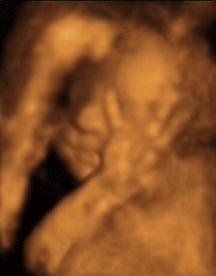

So far, so 3D... Time to add the 4th dimension!